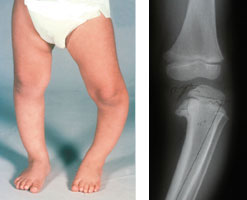

یکی از بیماری های شایع زانو در نوزادان زانوی ضربدری و زانو پرانتزی (قوس پا) می باشد. هنگامی که کودکی که دچار قوس پا است، می ایستد در حالی که پاهایش در کنار هم هستند، فضای مشخصی بین ساق پاها و زانوهای او وجود دارد. چنین چیزی می تواند ناشی از انحنای یک یا هر دو پا به سمت بیرون باشد. غالبا با راه رفتن کودک این ظاهر قوسی پاها بزرگنمایی می شود. در بسیاری از موارد قوس پا، کودک اضافه وزن قابل توجهی دارد. با همه این ها قوس پا در نوجوانان زیاد شایع نیست. ژنوواروم، زانوی درون گرد، زانوی پرانتزی یا پاکمانی ( واروس بیش از حد ) اختلال در مفصل زانو است که در آن زانو ها از هم فاصله زیادی می گیرند.

پزشک ارزیابی کودک را با معاینه فیزیکی کامل وی آغاز خواهد کرد. اگر کودک زیر ۲ سال باشد، وضعیت سلامتی اش خوب باشد و دچار قوس پای متقارن باشد (میزان قوس هر دو پا به یک اندازه باشد)، آنگاه به احتمال زیاد پزشک به پدر و مادر کودک خواهد گفت که در حال حاضر به آزمایش های بیشتر نیازی نیست. با این وجود، اگر پزشک متوجه شود قوس یکی از پاها نسبت به پای دیگر شدیدتر است، ممکن است آزمایش اشعه ایکس را برای ساق پاهای کودک توصیه کند. تصویر اشعه ایکس از پاهای کودک در حالت ایستاده می تواند بیماری بلانت یا نرمی استخوان را نشان دهد. اگر در اولین مراجعه به پزشک کودک بزرگ تر از ۵/۲ سال بوده دچار قوس پای متقارن باشد، به احتمال زیاد پزشک آزمایش اشعه ایکس را برای او توصیه خواهد کرد. احتمال ابتلای کودک به بیماری بلانت مربوط به دوران کودکی یا بیماری نرمی استخوان در این سن بیشتر است. اگر تصویر اشعه ایکس نشانه هایی از نرمی استخوان را نشان دهد، پزشک به منظور تایید وجود این اختلال برای کودک آزمایش خون تجویز خواهد کرد.

زانوی پرانتزی فیزیولوژیک تقریبا همیشه و با رشد کودک خودبخود اصلاح می شود. چنین چیزی معمولا در سن ۳ تا ۴ سالگی اتفاق می افتد. پیشرفت طبیعی بیماری نوجوان دچار بیماری بلانت درمان نکردن بیماری بلانت مربوط به دوران کودکی یا درمان نکردن نرمی استخوان منجر به پیشرفت و بدتر شدن قوس پا در دوران بعد از کودکی و نوجوانی می شود. در نهایت، این کودکان بواسطه فشارهای غیرعادی که روی مفاصل وارد می شوند دچار تغییر شکل پا (بخصوص زانوها) می شوند. احتمال تجربه درد ناشی از قوس پاها در نوجوانان دچار بیماری بلانت بیشتر است.